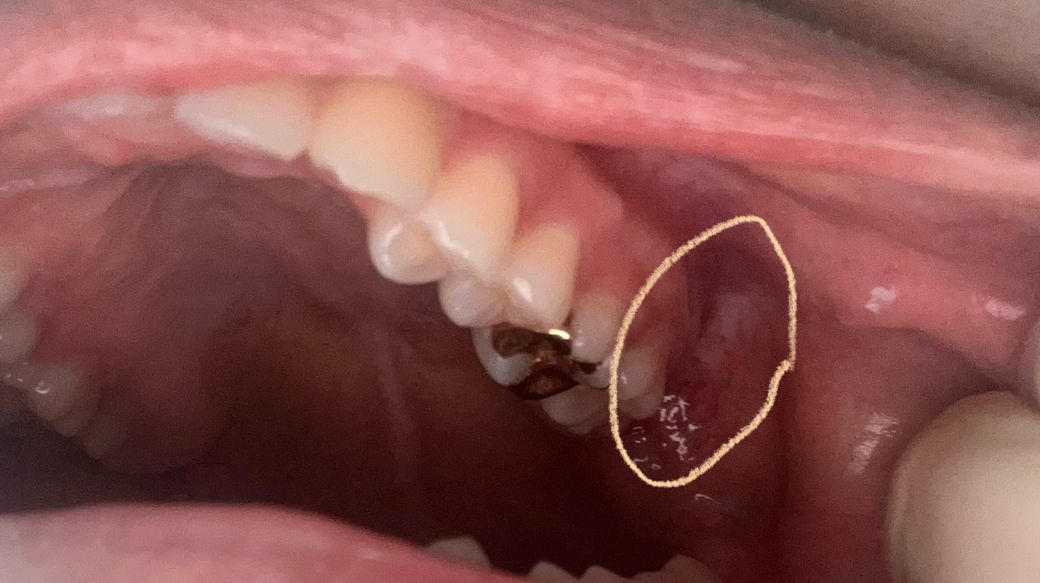

구강편평태선인가요? 어금니 뒤쪽이 빨간 핏줄들이 잘보이고 하얗게 됐습니다

구강편평태선인가요 오른쪽은 조금 하얗긴한데 핏줄도 잘 보이지않는데 왼쪽 어금니뒤쪽은 핏줄들도 너무 두드러지게보이고 그쪽이 하얗게 됐습니다 그물모양은 아닌것같은데 선처럼 쭉 되어있습니다

• 1번 째 사진